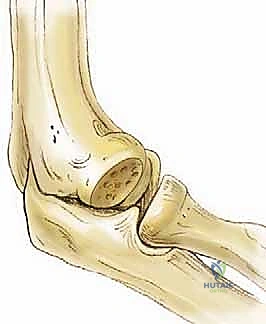

هنا يكمن بيت القصيد في موضوعنا. في هذا المفصل، يتصل الرأس الصغير (Capitellum) المستدير والمحدب للعظم العضدي البعيد مع الرأس الكعبري (Radial Head) المقعر. هذا المفصل يتحمل العبء الأكبر من قوى الضغط المحوري. عادةً ما يظهر المفصل الزندي العضدي بزاوية وحشية (Valgus Angle) تتراوح بين 11 و16 درجة. هذه الزاوية الطبيعية تؤدي إلى تركز قوى الضغط تحديداً في الجانب الوحشي (الخارجي) للمرفق أثناء الأنشطة الرياضية أو حمل الأشياء الثقيلة. هذا الضغط المتكرر والعنيف هو العامل الميكانيكي الرئيسي في نشأة التهاب العظم والغضروف السالخ (OCD).

التهاب العظم والغضروف السالخ (OCD) هو حالة مرضية بؤرية تصيب العظم تحت الغضروفي (Subchondral Bone). تبدأ القصة عندما ينقطع الإمداد الدموي الدقيق عن جزء صغير من العظم الموجود مباشرة تحت الغضروف المفصلي في الرأس الصغير (Capitellum).

نتيجة لنقص التروية الدموية (Ischemia)، يموت هذا الجزء من العظم (Avascular Necrosis). وبما أن الغضروف المفصلي يعتمد جزئياً في تغذيته ودعمه الميكانيكي على العظم السليم تحته، فإن الغضروف يبدأ بالضعف والتشقق. مع استمرار الحركة والضغط، يمكن أن ينفصل هذا الجزء الميت من العظم والغضروف المغطي له كلياً أو جزئياً، ليسقط كجسم حر (Loose Body) داخل تجويف المفصل، مما يشبه "الحصاة داخل الحذاء"، مسبباً ألماً مبرحاً وتوقفاً مفاجئاً في حركة المرفق.

4. المرحلة الرابعة (الجسم الحر - Loose Body): تسبح القطعة بحرية داخل المفصل، تاركة تجويفاً فارغاً في الرأس الصغير.